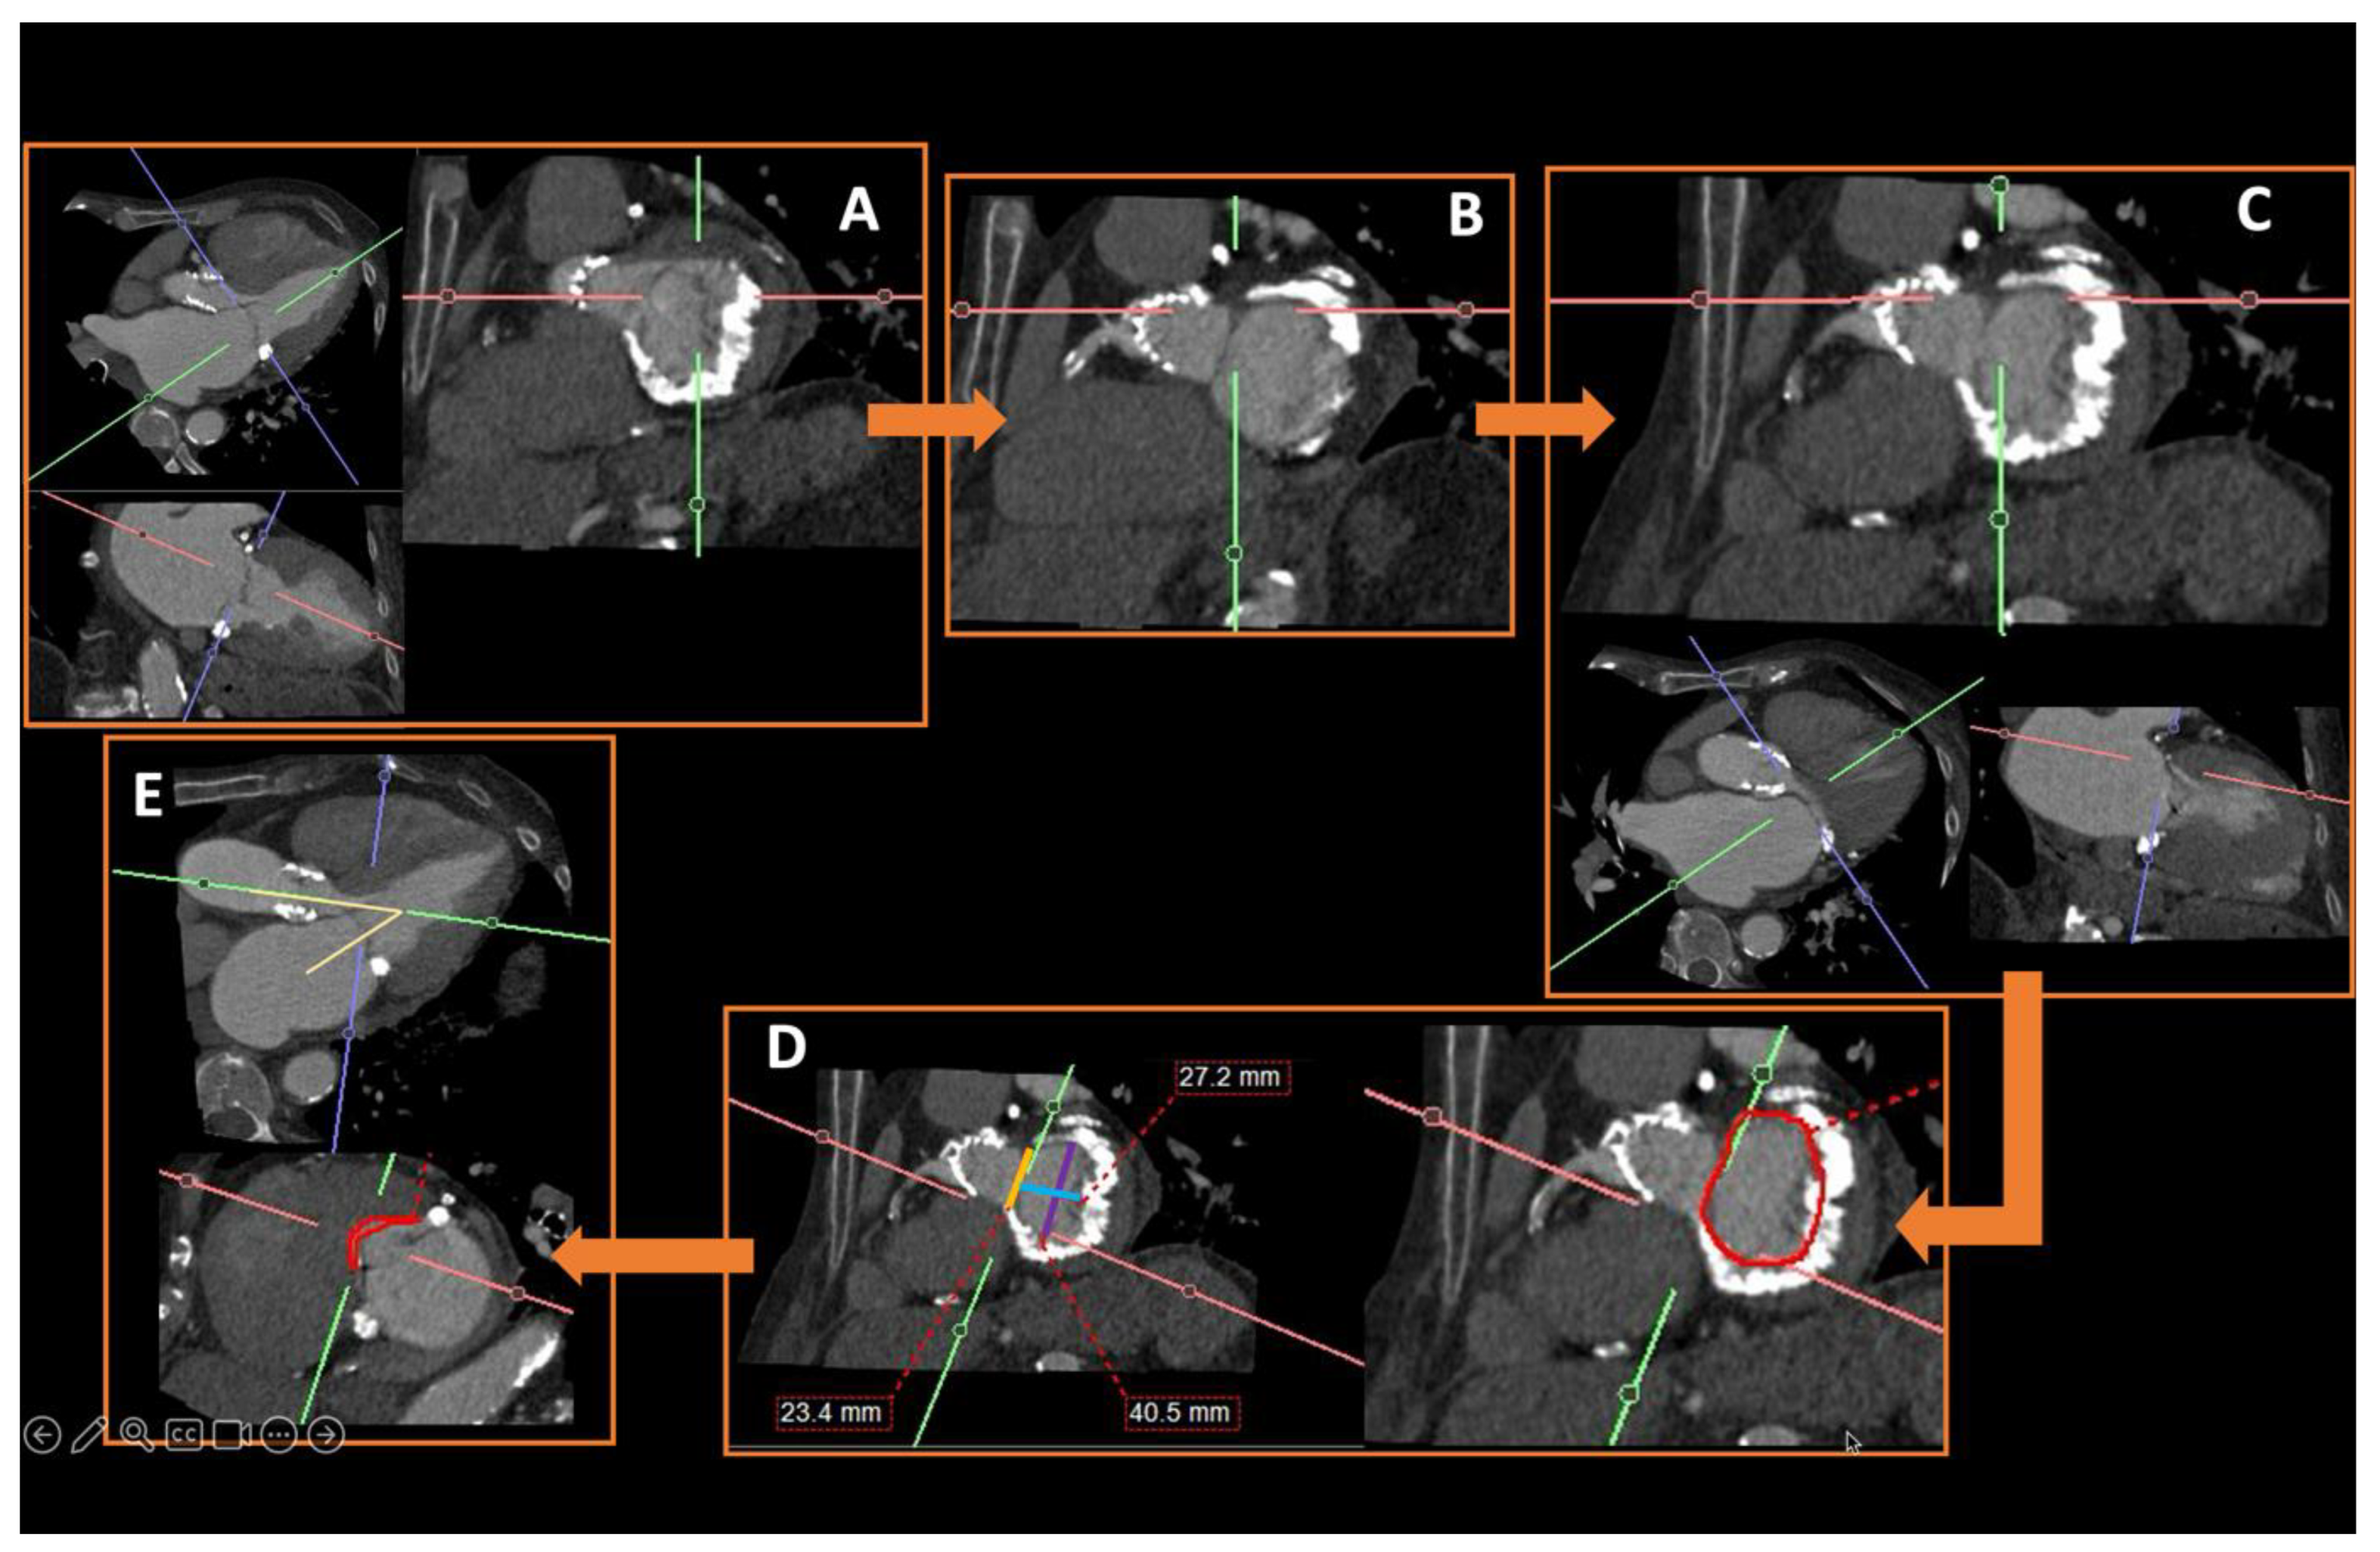

- Rudzinski, P.N.; Leipsic, J.A.; Schoepf, U.J.; Dudek, D.; Schwarz, F.; Andreas, M.; Zlahoda-Huzior, A.; Thilo, C.; Renker, M.; Burt, J.R.; et al. CT in Transcatheter-delivered Treatment of Valvular Heart Disease. Radiology 2022, 304, 4–17. [Google Scholar] [CrossRef]

- Maggiore, P.; Anastasius, M.; Huang, A.L.; Blanke, P.; Leipsic, J. Transcatheter Mitral Valve Repair and Replacement: Current Evidence for Intervention and the Role of CT in Preprocedural Planning—A Review for Radiologists and Cardiologists Alike. Radiol. Cardiothorac. Imaging 2020, 2, e190106. [Google Scholar] [CrossRef]

- Faggioni, L.; Gabelloni, M.; Accogli, S.; Angelillis, M.; Costa, G.; Spontoni, P.; Petronio, A.S.; Caramella, D. Preprocedural planning of transcatheter mitral valve interventions by multidetector CT: What the radiologist needs to know. Eur. J. Radiol. Open 2018, 5, 131–140. [Google Scholar] [CrossRef] [PubMed]